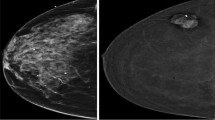

CESM (contrast-enhanced spectral mammography) is an efficient tool for detecting breast cancer because of its image characteristics. However, among most deep learning-based methods for breast cancer classification, few models can integrate both its multiview and multimodal features. To effectively utilize the image features of CESM and thus help physicians to improve the accuracy of diagnosis, we propose a multiview multimodal network (MVMM-Net).

The experiment is carried out to evaluate the in-house CESM images dataset taken from 95 patients aged 21–74 years with 760 images. The framework consists of three main stages: the input of the model, image feature extraction, and image classification. The first stage is to preprocess the CESM to utilize its multiview and multimodal features effectively. In the feature extraction stage, a deep learning-based network is used to extract CESM images features. The last stage is to integrate different features for classification using the MVMM-Net model.